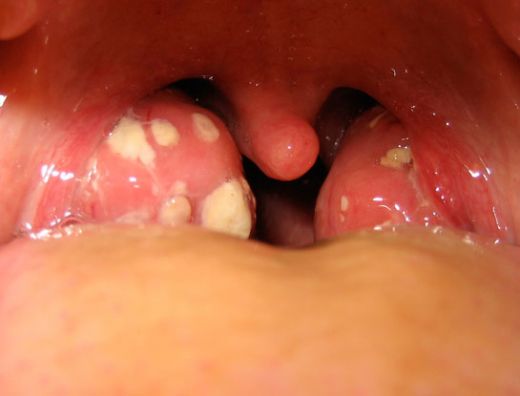

Bademcik İltihabı Nedir?Bademcik iltihabı, genellikle viral veya bakteriyel enfeksiyonlar sonucunda bademciklerin iltihaplanmasıdır. Bademcikler, boğazın arka tarafında bulunan ve vücudu enfeksiyonlara karşı koruyan lenfatik dokulardır. Bu durum, genellikle çocuklarda daha sık görülür, ancak her yaş grubunu etkileyebilir. Bademcik iltihabı, boğaz ağrısı, yutma zorluğu, ateş ve genel bir rahatsızlık hissi ile kendini gösterir. Bademcik İltihabının Belirtileri Bademcik iltihabının belirtileri genellikle şunlardır:

Bademcik İltihabının Nedenleri Bademcik iltihabının başlıca nedenleri şunlardır: